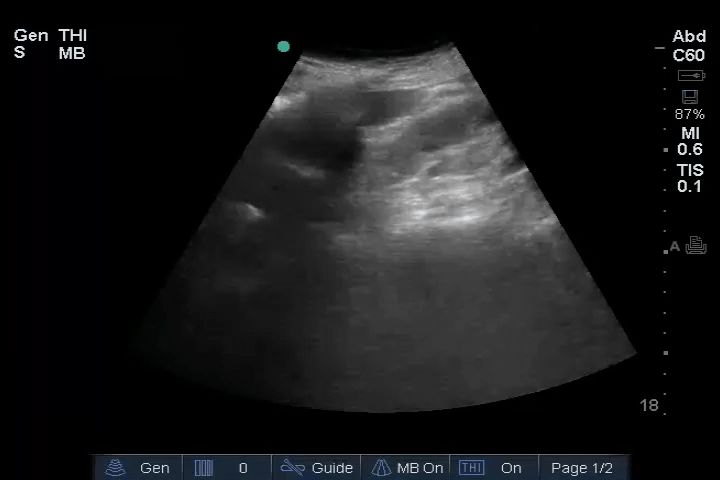

11_Heart_A4CH – Dilated RV, RA embolus

Heart: Dilated right ventricle (RV), most clearly visualized in the PSAX view. An embolus is visible in the right atrium (RA).